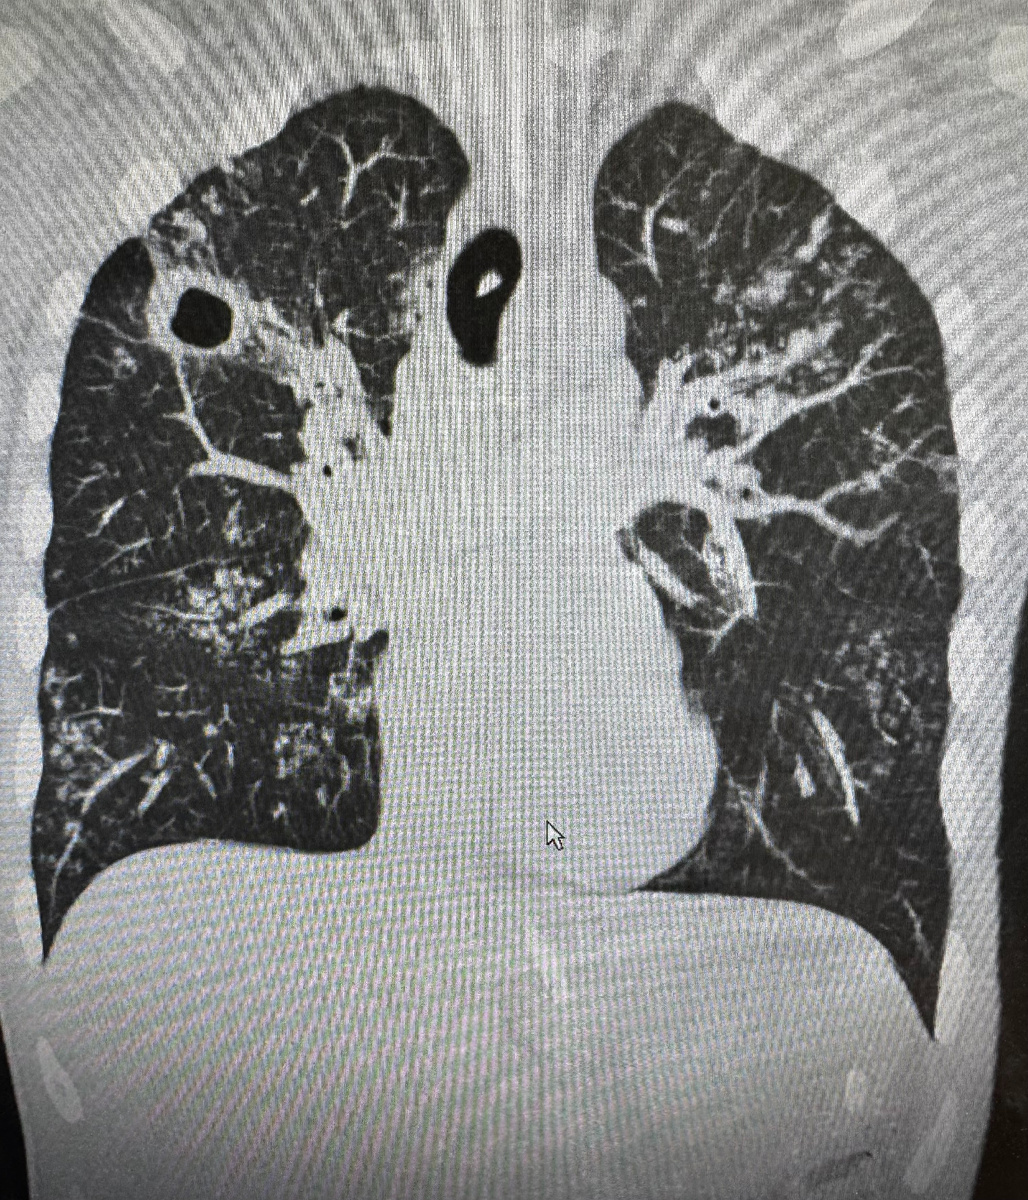

Туберкулез легких на КТ. Видна полость распада справа и многочисленные очаги уплотнения в обоих легких.